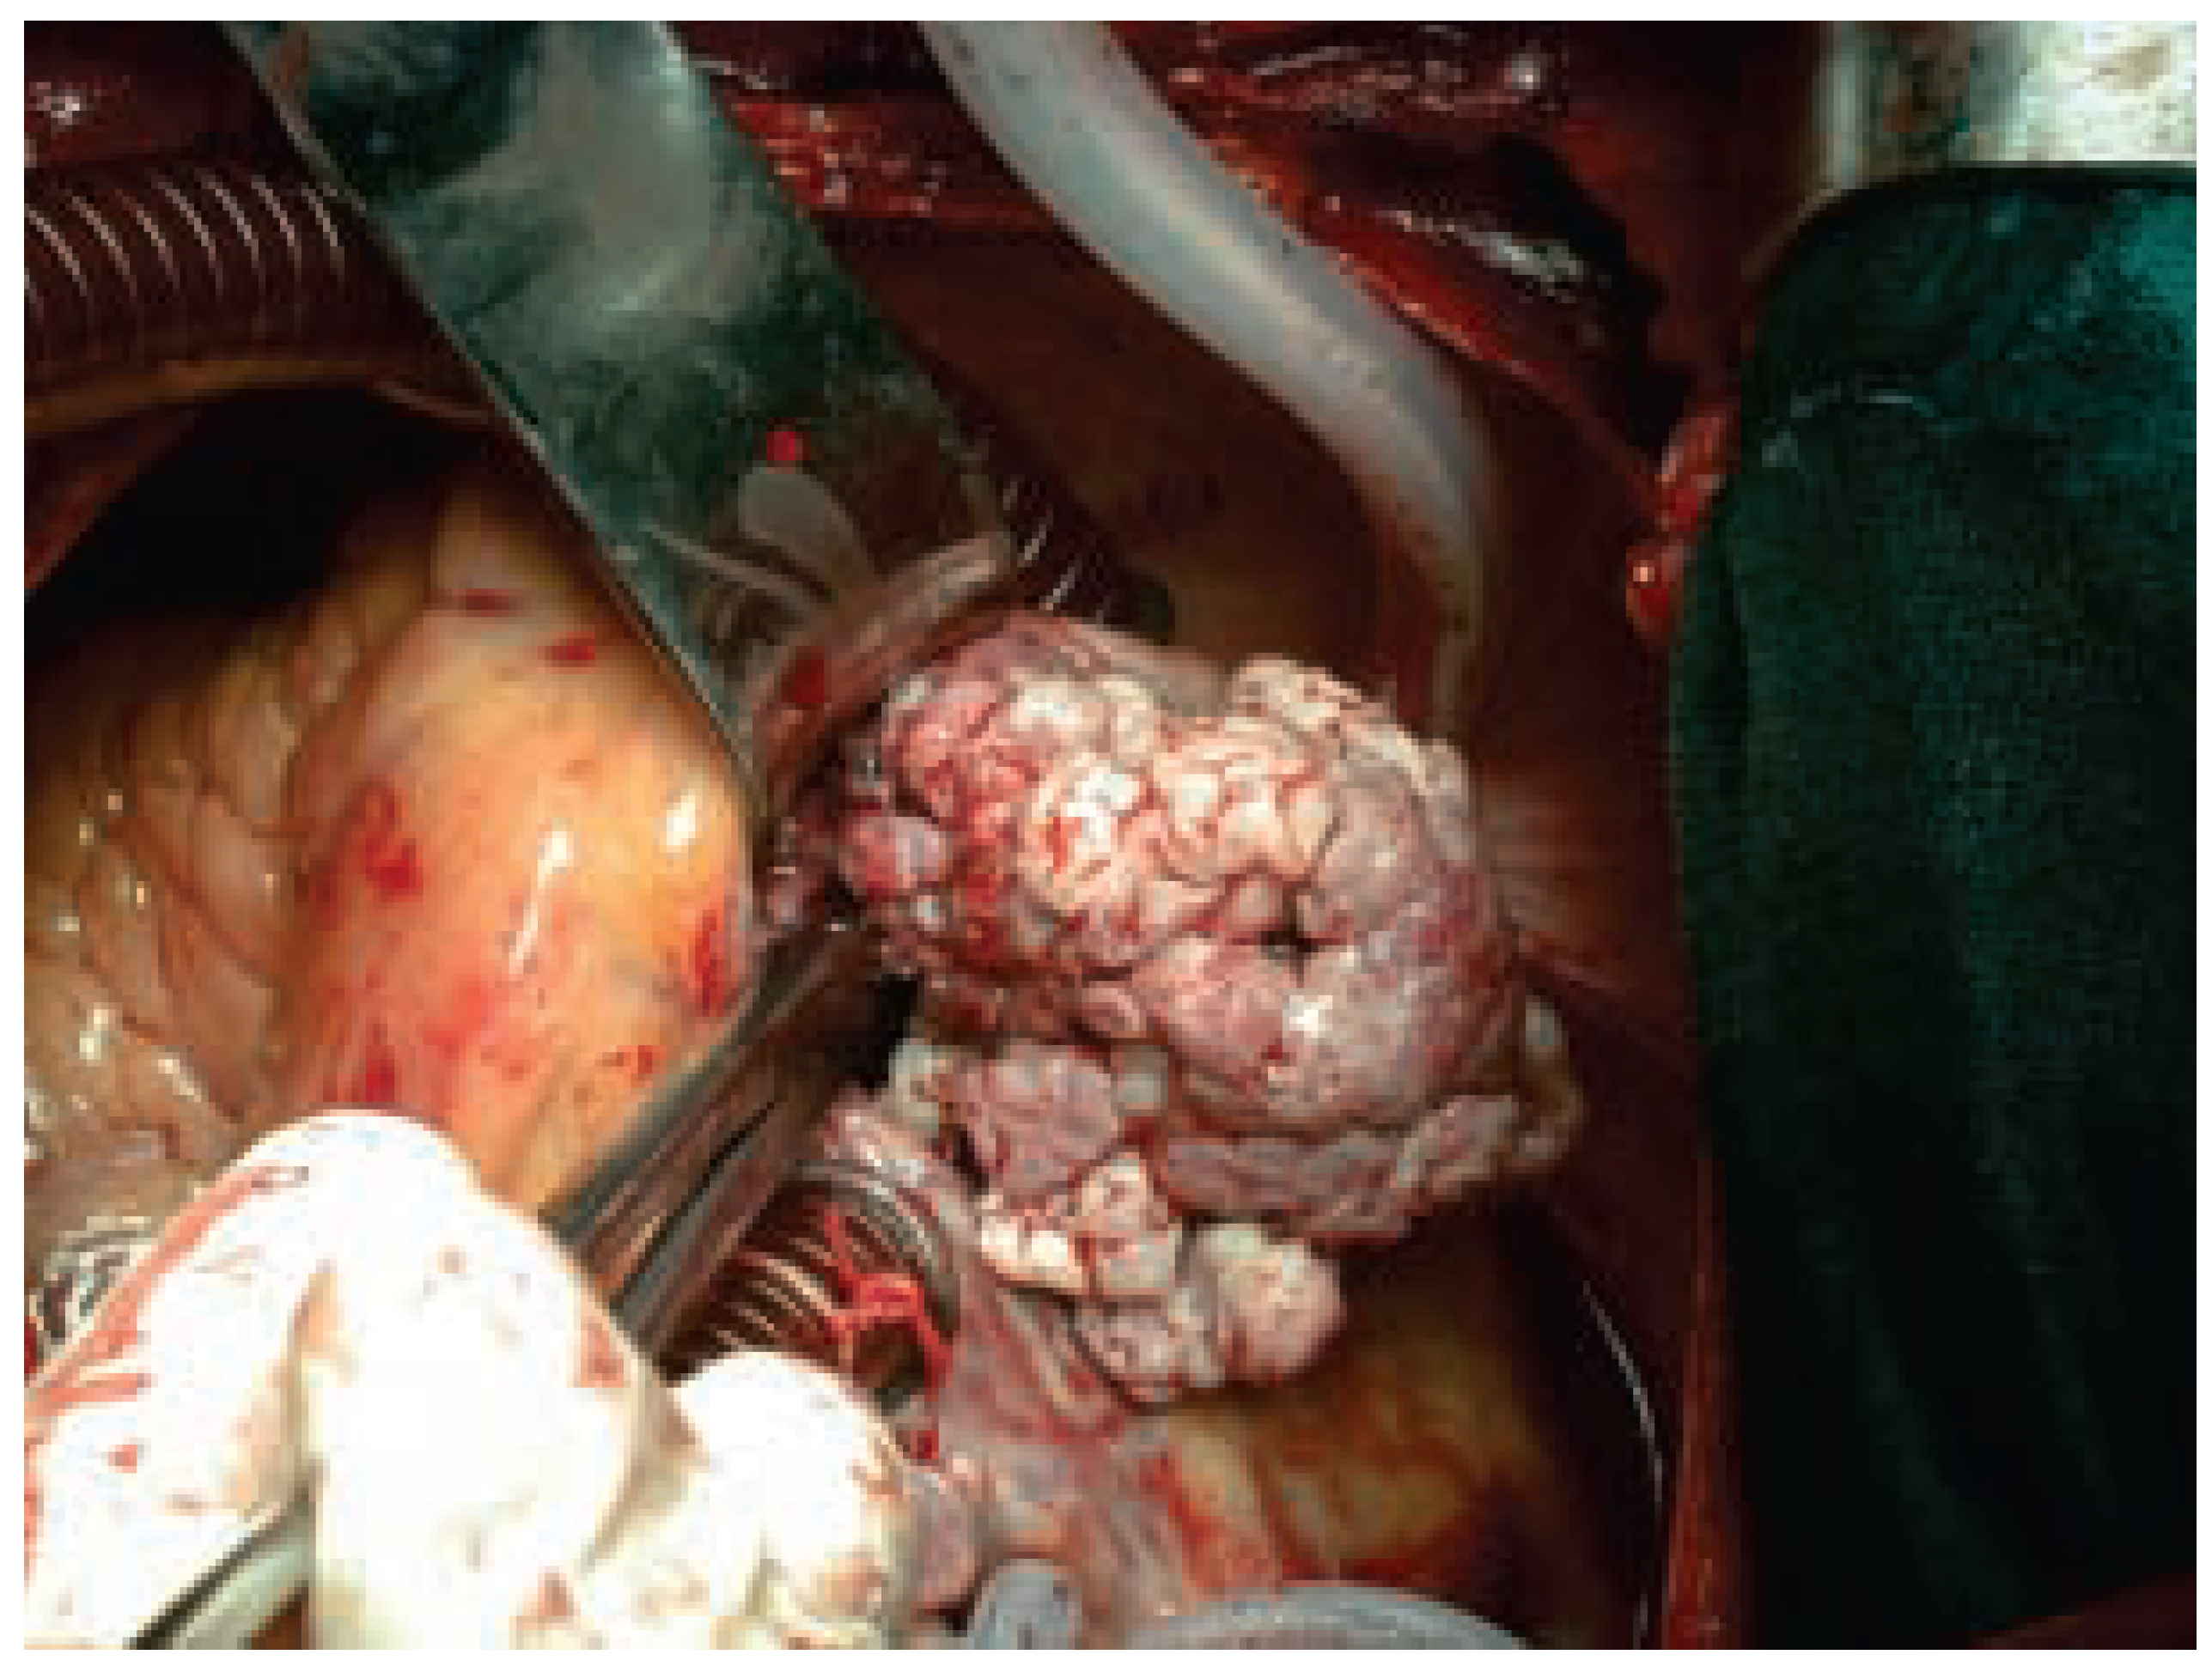

Abbildung 3. Der intraoperative Situs nach bikavaler Kanülierung und Eröffnung des rechen Vorhofs förderte eine riesige blumenkohlartige Vegetation zutage, welche beide Elektroden umscheidete und an der Trikuspidalklappe festgewachsen war (vgl. Abb. 2). Histologisch bestand das ganze Konvolut aus Candida-albicans-Kolonien.

Bei Entfernung von mehreren Sonden, die häufig auf Vorhofniveau stark miteinander verwachsen sind und damit eine endovenöse Entfernung erschweren, muss eine chirurgische Entfernung vorgenommen werden. Diese kann bei anatomisch einfachen Verhältnissen in bikavaler Einflussstauung durchgeführt werden, häufiger aber erfordert sie eine offene Herzchirurgie an der Herz-Lungen-Maschine. Letztere ist auch dann notwendig, wenn echo kardiographisch eine schwere Verwachsung der endovenösen Kabel mit der Trikuspidalklappe oder gar eine hämodynamisch relevante Trikuspidalinsuffizienz vorliegt (Abb. 2). In diesen Fällen müssen die Elektroden unter Sicht minutiös von der Trikuspidalklappe abgetrennt und gegebenenfalls die Trikuspidalklappe rekonstruiert werden. Der Vorteil der chirurgischen Technik liegt sicherlich darin, dass grosse endokarditische Auflagerungen und Thromben unter Sicht entfernt werden können (Abb. 3). Dennoch kommt es auch bei der chirurgischen Technik in bis zu 17% der Fälle zu szintigraphisch nachweisbaren Embolien, was aber im Vergleich zu 30% mit der Lead-extraction-Technik ein geringeres Problem darstellt [1]. Obwohl die Erfolgsrate der chirurgischen Technik annähernd 100% erreicht, sollte diese Methode nur angewandt werden, wenn eine endovenöse Entfernung mittels der Lead-extraction-Technik nicht möglich oder zu risikoreich ist, da die operative Mortalität bis zu 17% beträgt [1]. Im Falle einer chirurgischen Entfernung sollte unbedingt eine vorgängie Koronarangiographie erfolgen, da perioperative Infarkte bei dieser Population keine Seltenheit darstellen. Bei Vorliegen hämodynamisch relevanter Koronarstenosen sollte in der gleichen Operation eine Myokardrevaskularisation vorgenommen werden.